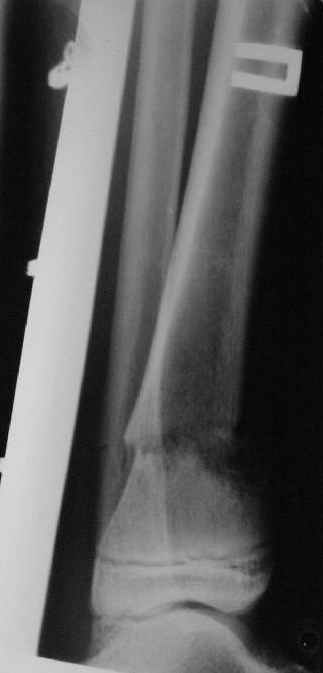

Ребенок 12 лет, поступил после падения с высоты примерно 2,5м.

Перелом костей н\3 правой голени со смещением. Перелом большеберцовой кости можно охарактеризовать как компрессионно-оскольчатый.

A> Перелом костей н\3 правой голени со смещением.

Это от 13.10.04? А это близкие к первичным снимки?

A> Перелом большеберцовой

A> кости можно охарактеризовать как компрессионно-оскольчатый.

Есть один осколок... Ма-аленький такой... Но из-за этого стоит ли весь

перелом характеризовать как оскольчатый?

Нормальный такой перелом... "шарнирный" я бы сказал... ну да есть

элемент сдавления (компрессии) по оси... и что?

A>> Перелом костей н\3 правой голени со смещением.

AVM> Это от 13.10.04? А это близкие к первичным снимки?

Не смешно :) Зачем я о месяцах лечения писал?

Есть даже тень периостальной костной мозоли и сросшийся перелом

малоберцовой кости.

Первичные